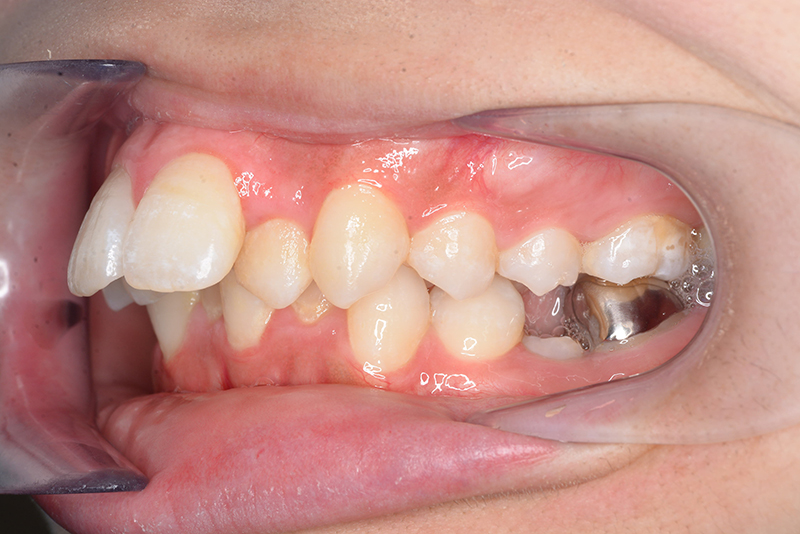

初診時

FP・IOP

顔貌所見 正貌はほぼ対象。側貌はconvex type、著しい口唇閉鎖不全が認められた。

口腔内所見 over jet 11.5mm、over bite 5.5mm、右側臼歯関係Full ClassⅡ級、左側end onⅡ級、上顎顎歯列はテーパー型であり、上顎中切歯は押し出されるように大きく唇側傾斜していた。下顎前歯部は叢生を呈しており、左下5は歯冠長が短く半埋伏していた。

セファロ所見 下顎骨体部は小さくないものの下顎枝は短く、下顎頭は後方に位置付き中顔面高は高いため、下顎はクロックワイズローテーションしており、前後的にはII級の骨格形態を示していた。

パノラマ所見 上下顎両側第三大臼歯は埋伏していた。下顎右側大臼歯から犬歯まで近心傾斜し、左側においては左下5を境に大臼歯は近心傾斜、近心の歯は遠心方向へ傾斜が認められた。